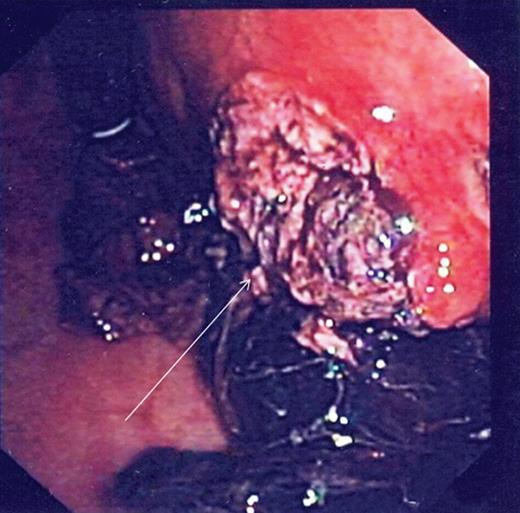

During the second day of admission, the patient passed out large amounts of melena and had an episode of haematemesis. She also developed tacchycardia with heart rate increasing to 110–120 b.p.m. Repeat blood investigations showed that haemoglobin had fallen from 6.8 to 5.3 g/dl despite blood transfusion. An emergency oesophagogastroduodenoscopy was performed. Findings were that of grade 1 oesophageal varices with no features of variceal bleed. There was a large clot in the fundus and cardia of the stomach. After attempted removal of the blood clots with flushing, the patient developed torrential bleeding necessitating intubation for airway protection. The bleeding eventually ceased spontaneously and the source of bleeding was identified to be originating from a large ulcer crater in the greater curve with an overlying clot (Fig. 1). Endoscopic ultrasound was performed which showed a 10 cm mass lesion abutting the stomach wall and extending into the peritoneal cavity (Fig. 2). The preliminary impression was that of a bleeding GI stromal tumour and care was transferred to the surgical team for consideration of surgical intervention.

Endoscopy showing ulcer crater in greater curvature of stomach.